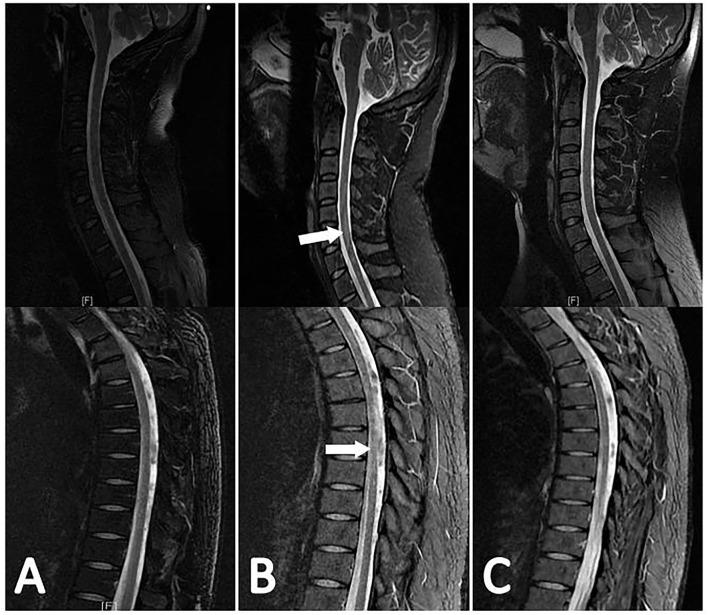

We conducted a retrospective study in our institution. Patients with TBM who were consecutively admitted during the period of August 2015 to December 2019 were included. We reviewed the demographic characteristics, clinical, laboratory and MRI findings, and clinical outcomes of all of the included patients. The diagnosis of myelitis was identified by a hyperintensity on T2-weighted images that were associated with cord edema, enlargement, and marginal or no enhancement on contrast-enhanced images.

A total of 114 patients were included. Myelitis occurred in 19 (16.7%) patients, five of whom paradoxically developed myelitis. The common clinical signs of myelitis were paraparesis (738.9%), quadriparesis (844.4%), urinary retention or constipation (1,477.8%), and paresthesias in the lower limbs (1,052.6%). In the MRI findings, the hyperintensities on T2-weighted images involved more than 3 spinal cord segments. Myelitis was often combined with other forms of spinal cord injury, including 10 patients (52.6%) with spinal meningeal enhancement, 7 patients (36.8%) with enlargement of the central canal of the spinal cord, 6 patients (31.6%) with tuberculoma, and 4 patients (21.1%) with arachnoiditis and 1 patient (5.3%) with cerebrospinal fluid (CSF) loculations. None of the 5 patients with paradoxical myelitis were complicated with spinal meningeal enhancement and arachnoiditis, while 4 patients were complicated with enlargements of the central canal of the spinal cord. In multivariable analysis, a grade III disease severity on admission [ = 0.003, odds ratio (OR) = 8.131, 95% CI: 2.080-31.779] and high CSF protein ( = 0.033, OR = 1.698, 95% CI: 1.043-2.763) were independent risk factors for myelitis. After the 6 months follow-up, myelitis ( = 0.030, OR = 13.297, 95% CI: 1.283-137.812) and disturbance of consciousness ( = 0.042, OR = 12.625, 95% CI: 1.092-145.903) were independent risk factors for poor outcomes.